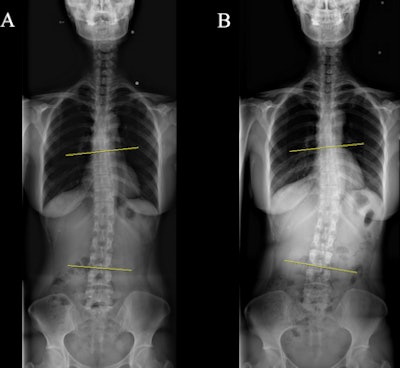

The first x-ray was performed within 60 days postoperatively and a follow-up x-ray was conducted ≥ 300 days later. Spinal curvature was measured using the Cobb angle on whole-spine x-rays, with the greatest curvature marked between two lines on the film. Scoliosis was defined as ≥ 10° of curvature.

At initial radiological assessment, the mean Cobb angle was 5.4° and all but one of the 200 patients had mild scoliosis (10°-20°), with no significant differences in Cobb angles and proportions of scoliosis among the three surgery groups, according to the findings.

The mean interval between the initial and follow-up x-ray was 28.46 ± 13.39 months (median, 26.41 months). In follow-up x-rays, the mean change and mean absolute value of the change in Cobb angle were 0.4 ± 1.65° and 1.25 ± 1.15°.